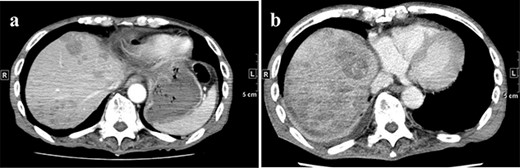

A 77-year-old man was referred to the Department of Gastroenterology at our hospital for suspicion of hepatocellular carcinoma and cancerous peritonitis. He was scheduled to be hospitalized for a thorough examination at a later date. However, 3 days after his first visit, he returned to the Emergency Department with a complaint of abdominal distension. He was hospitalized on the same day with a diagnosis of intra-abdominal bleeding due to a ruptured tumor in the lateral section of the liver. Computed tomography (CT) and magnetic resonance imaging (MRI) revealed a tumor with a maximum diameter of 8 cm in the lateral hepatic region and ascites around the liver and in the pelvic floor. Dynamic CT showed blood vessel-like early staining inside the tumor, and the contrast effect gradually enhanced (Fig. 1). During gadolinium ethoxybenzyl diethylenetriamine pentaacetic acid-enhanced MRI, this contrast effect gradually increased from the peripheral part toward the hepatocyte phase from the arterial phase (Fig. 2). Levels of tumor markers (alpha-fetoprotein, protein induced by vitamin K absence or antagonist-II, carcinoembryonic antigen and carbohydrate antigen 19–9) were within the normal range (Table 1). Based on the imaging findings, a diagnosis of spontaneously ruptured hepatic hemangioma was made. Since the patient’s general condition was stable and there were no findings suggestive of active bleeding, he decided to undergo elective surgery. Thus, he was not requested to continue being hospitalized and was discharged. Six days after discharge, he was transported to the emergency room in a state of shock and was hospitalized the same day. With the diagnosis of hemorrhagic shock due to re-rupture of the liver tumor (Fig. 3), emergency transarterial embolization (TAE) was performed. No apparent extravasation was observed on angiography, and A3 was embolized. Seven days later, he underwent left lateral hepatic segmentectomy. The postoperative course was generally good. The post-ruptured tumor was found in the left lateral segment, the cut surface was white, the edges were brown and the boundaries were unclear (Fig. 4). Histopathological examination revealed that sections of the white and brown parts of the margin were viable tumors, showing highly atypical spindle-shaped cells, arranged like sinusoidal vessels and partly solid, and there were many mitotic figures. There was no capsule, and the tumor infiltrated the surrounding liver parenchyma (Fig. 5a–c). Immunostaining showed CD31 (+), CD34 (partially positive), CK-CAM5.2 (−), α-SMA (−), HMB45 (indeterminate) and p53 (+), and the patient was diagnosed with hepatic angiosarcoma (Fig. 5d). Fever was observed 21 days after surgery, and CT was performed, revealing multiple masses in the liver (Fig. 6a). Another CT scan was performed 27 days postoperatively, which suggested that the liver masses were rapidly increasing; hepatic angiosarcoma recurrence was then confirmed (Fig. 6b). The patient requested the best supportive care at home and was discharged 31 days after the operation. He died at home 36 days after surgery.

CT at initial admission points out a tumor with a maximum diameter of 8 cm in the lateral hepatic region and ascites around the liver. Dynamic CT shows blood vessel-like early staining inside the tumor, and the contrast effect gradually enhances. (a) Arterial phase, (b) equilibrium phase. CT, computed tomography.